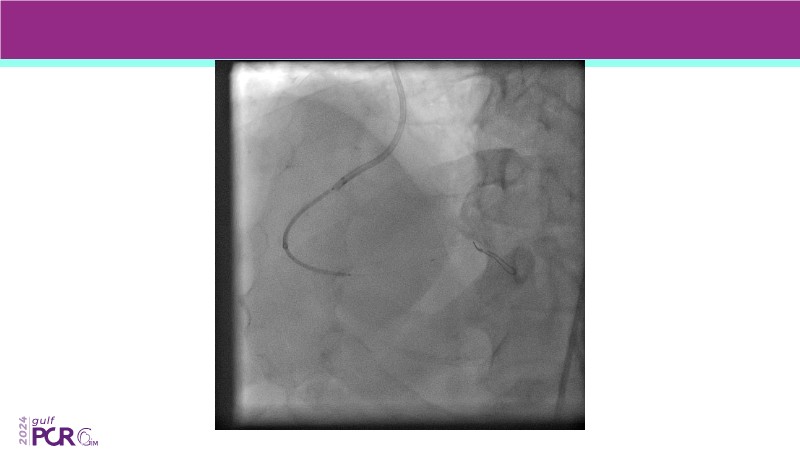

Explore the future of complex PCI with Meril Life’s advanced solutions. Learn about thin-strut platforms, dedicated stents for side branches and diffuse lesions, the role of drug-eluting balloons in metal-free PCI, and the clinical potential of the Myval THV technology.

- To discover your next gen complex PCI toolkit with thin strut platforms and dedicated stenting solutions for managing side branch and long diffused lesions